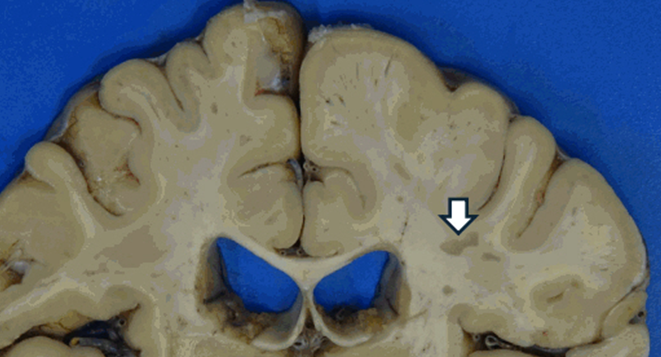

Glavna patološka promjena u moždanom tkivu kod oboljelih od multiple skleroze jest plak. Plak predstavlja oštro ograničeno područje u kojem je došlo do demijelinizacije moždanog tkiva. Drugim riječima, jasno se može uočiti granica između oštećenog i zdravog tkiva mozga. Karakteristično je da se plakovi mogu pojaviti na različitim mjestima u središnjem živčanom sustavu i da njihova lokalizacija varira od osobe do osobe.

Do sada su zabilježeni plakovi u:

• područjima moždanih komora

• malom mozgu

• kralježničnoj moždini

• vidnom živcu

• njušnom živcu

• pa čak i u sivoj tvari mozga

Ova varijabilnost u lokalizaciji plakova objašnjava zašto simptomi bolesti mogu biti vrlo različiti kod različitih pacijenata. Primjerice, ako plak zahvati vidni živac, pacijent može imati izražene smetnje vida, dok zahvaćenost malog mozga može dovesti do poremećaja ravnoteže i koordinacije. Broj plakova, njihov oblik i veličina također variraju od pacijenta do pacijenta.

Osim toga, plakovi se mogu razlikovati i prema boji:

• sivi plakovi ukazuju na kroničnu fazu bolesti

• crveni plakovi javljaju se u akutnoj fazi bolesti

• žućkasti plakovi nastaju zbog prisutnosti velikog broja upalnih stanica poput makrofaga

Ponekad plakovi mogu razviti i cistične promjene, odnosno šupljine unutar samog plaka, što je obično povezano s težim kliničkim tijekom bolesti i lošijom prognozom.